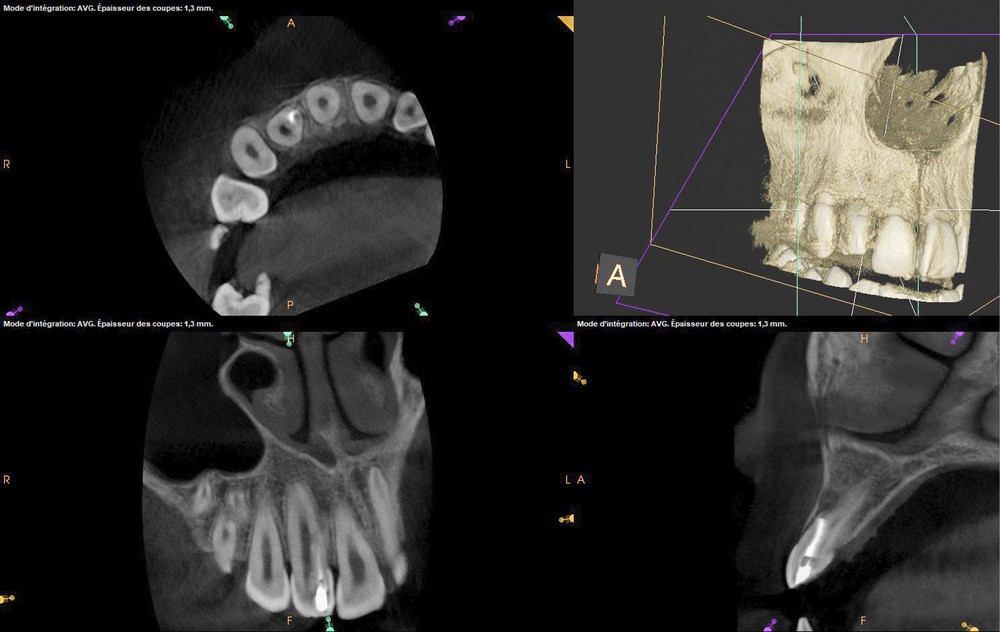

La patiente, âgée de 12 ans, s’est présentée à ma consultation avec une demande du chirurgien de réaliser le traitement endodontique de la 12 avant le curetage sous anesthésie générale. La radiographie périapicale préopératoire a mis en évidence une anatomie complexe. Les tests préopératoires ont montré un sondage parodontal sain, une percussion positive et un test au froid positif. La patiente présentait également une fistule vestibulaire active. Le Cone Beam a mis en évidence la présence d’une dens in dente et d’une lésion imposante ainsi qu’une palatoversion importante de la racine de la 12. La lésion est-elle responsable de ce mouvement dentaire ? (fig. 1, 2 et 3).